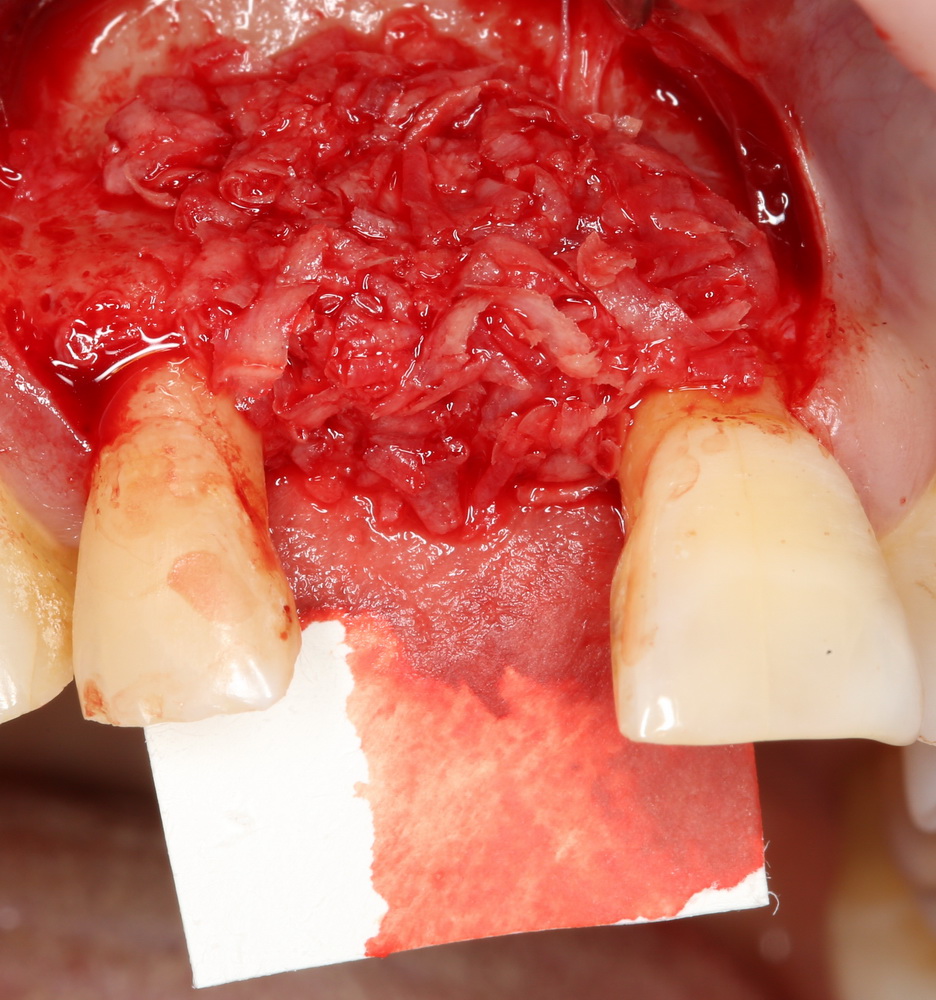

ТОЛЬКО аутокостная стружка содержит клетки, необходимые для регенерации костной ткани. Поэтому ее можно использовать как изолировано:

Так и в смеси с ксенотрансплантатами. Например, Geistlich Bioss:

Оптимальное соотношение — 50/50, но допускается и 30/70.

Затем укладывается и конфигурируется аутокостная стружка: